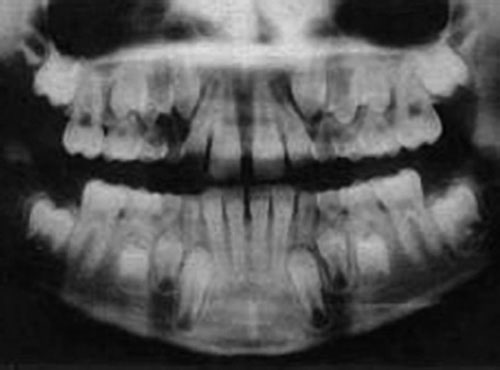

Find ugly duckling stock images in hd and millions of other royalty free stock photos illustrations and vectors in the shutterstock collection. Ugly duckling stage quick reference a stage of dental development usually between the ages of 7 and 12 years preceding the eruption of the permanent canines when the upper central and lateral incisors are tipped laterally due to the crowding created by the unerupted canines to produce a midline space median diastema. Ugly duckling download free clip art with a transparent background on men cliparts 2020.

55 ugly duckling image clipart. Ugly duckling stage is a transient form o. This video was uploaded from an android phone.